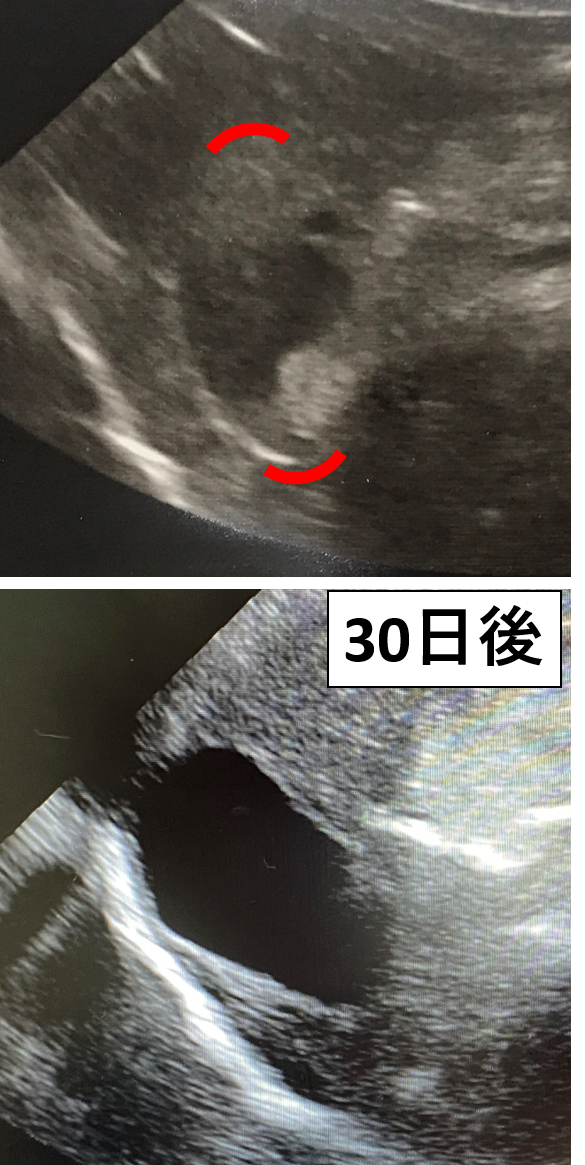

犬 胆泥症 原因-胆泥 をかたちづくっているのは コレステロール や 黄疸色素 ( ビリルビン )、 カルシウム などの微細な 結晶 が 胆嚢壁 から分泌される 粘液 に包まれたものと考えられますが、他にも 炎症 によっこんにちは。獣医師の清水いと世です。 今回は、わんちゃんの胆泥症について説明します。 前編は、胆泥症の原因や検査方法や症状について、後編は治療や予防方法について説明します。 犬の胆泥

胆泥症・胆石症について 胆嚢は、胆汁を産生し貯留する器官です。 胆汁には、脂肪を分解し水に溶けやすい状態に(乳化)する役割を持っています。 胆嚢に貯えられた胆汁は、元々サラサラの水胆泥を生じさせた原因や疑われる原因があれば、それを取り除きます。 そのために、 犬の胆泥症 <前編> で説明した原因追及のための検査結果が重要になります。 肝臓の異常が認められるので